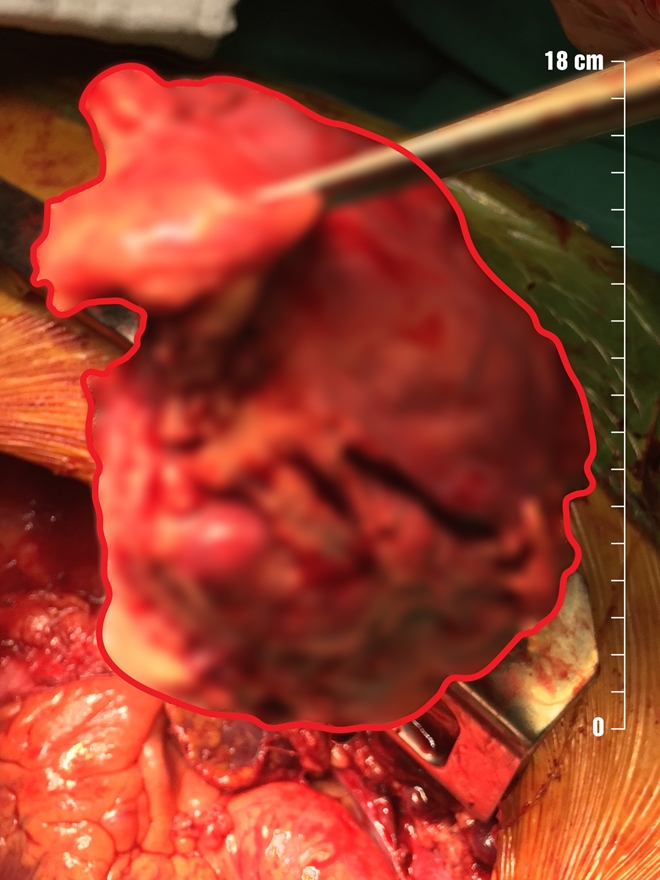

Ngày 17/6, các bác sĩ Khoa Phẫu thuật Tim Mạch – Lồng Ngực Bệnh Viện Đa Khoa Xuyên Á (BVXA) cho biết, họ đã phẫu thuật thành công cắt khối u trung thất (U ở phần lồng ngực giữa hai lá phổi) cho một nam bệnh nhân.

Sau khi thăm khám, các bác sĩ xác định có 1 khối u xuất phát từ trung thất trước, xâm lấn rộng vào màng ngoài tim, tĩnh mạch vô danh, thần kinh hoành bên trái, động mạch phổi và lan ra sau dính vào động mạch chủ ngực xuống.

Khối u trung thất được phẫu tích, bóc tách khỏi cơ thể bệnh nhân an toàn.

Sau 2 giờ phẫu thuật, khối u khoảng 13x15x18cm (to bằng quả tim của bệnh nhân) được lấy ra thành công.

Khối u trong vùng trung thất của bệnh nhân khi chưa mổ.

Theo các bác sĩ, đây cũng là một trường hợp mang khối u trung thất to như vậy nhập viện, khối u tại vị trí trung thất thường gây nên các triệu chứng chèn ép các cơ quan bên trong trung thất (như mạch máu, thần kinh), hay xâm lấn thành ngực và gây nên nhiều triệu chứng như đau ngực, ho khan, yếu cơ, phù nửa trên người, khàn giọng, loạn nhịp tim, khó thở, đau ngực,...

Các khối u trong trung thất thường có tỷ lệ ác tính cao và phần lớn cần phải điều trị phẫu thuật càng sớm càng tốt, khi u chưa xâm lấn rộng sẽ dễ dàng hơn về mặt kỹ thuật cũng như kéo dài thời gian sống hơn cho bệnh nhân.